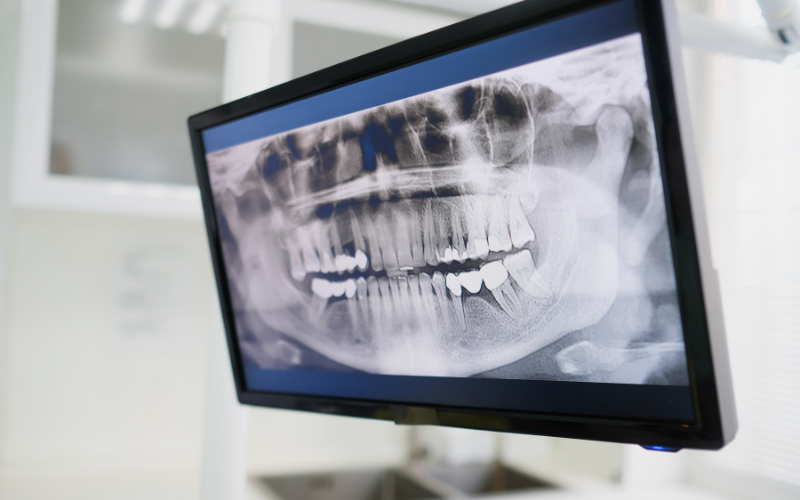

親知らずの状態を正確に把握するためには、見た目だけでなく画像検査が欠かせません。一般的に行われるレントゲン検査では、歯の位置や向き、埋まっているかどうか、隣の歯との距離などを確認することができます。特に、歯ぐきの中に埋まっている親知らずや、斜め・横向きに生えているケースでは、肉眼では判断できない情報を得るために重要な検査です。

さらに必要に応じてCT撮影を行うことで、三次元的に骨の中の位置や神経との距離、歯の根の形態などをより詳細に把握することが可能になります。埼玉県行田市の歯医者・おおいし歯科医院でも、こうした画像診断をもとに、抜歯の必要性や難易度を評価し、患者さま一人ひとりに適した治療方針を検討していきます。

神経や骨との位置関係の確認が重要な理由

親知らずの抜歯において特に重要となるのが、歯と神経・骨との位置関係の把握です。下顎の親知らずの近くには「下歯槽神経」という重要な神経が通っており、この神経に近接している場合、抜歯の際にしびれなどの神経症状が生じるリスクがあります。そのため、事前にCTなどで正確な位置関係を確認し、リスクを適切に評価することが重要です。